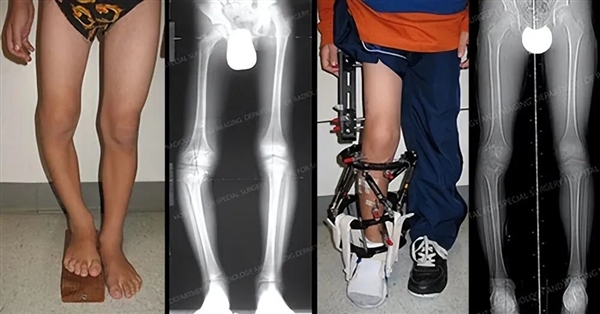

在过去,只有腿部有问题(例如畸形和长短腿)影响正常生活的人,才会冒险选择这样的治疗方式,而如今,却成了人们改变外观的一种手段。

在医学上,缩短术专业术语是“股骨近端干骺端缩短术”,同样,在我们国家,只能针对病理性修复,但在土耳其伊斯坦布尔,只要你愿意就能做,有一家诊所2年不到,就做了10个。

腿部畸形矫正案例